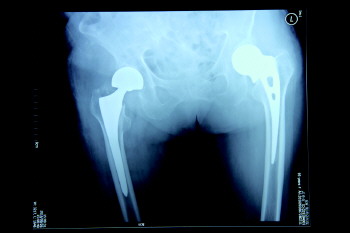

术前X光图